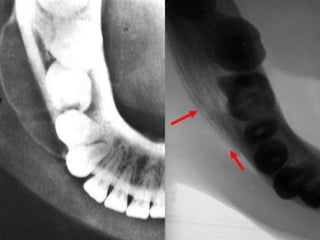

Este documento describe las radiografías oclusales y panorámicas, incluyendo sus usos y técnicas. Las radiografías oclusales se utilizan para examinar grandes áreas de los maxilares y se colocan entre las superficies oclusales cuando el paciente muerde suavemente. Las panorámicas permiten ver los maxilares y la mandíbula en una sola imagen. El documento también explica diferentes tipos de radiografías periapicales y sus ángulos de inclinación.